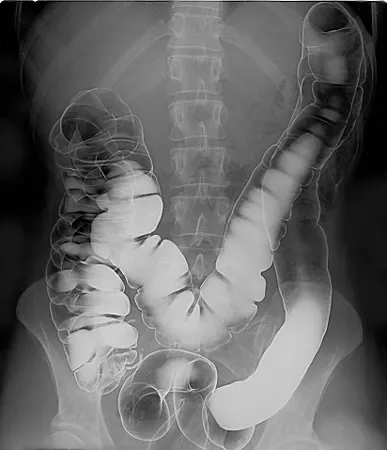

基本上 X 光現在主要用來看骨頭或腫瘤等等這種非常緻密的結構,但要看到其他內臟也是可以只是相對沒那麼清晰,除非額外施加壓力來提升組織的緻密程度,例如乳房造影(mammography)就得夾胸才能照,但會讓病人感受到一定程度的痛楚。

為了更清楚地看見除了骨頭以外的其他內部構造,後來陸續有了各種改良技術,像是在底片塗上螢光染料來間接成像的「螢光透視攝影(fluoroscopy)」,X 光會打在螢光染料上轉換成可見光,再對它的訊號放大,就可以大幅降低 X 光的照射量,也就可以讓病人照更久,拍攝實時的動態影像;還可以利用注射或直接喝下顯影劑來觀測消化道內顯影劑的流動情形,因為顯影劑會含有原子序大的元素(例如碘和鋇)讓 X 光不易穿透,因此增強影像的對比。